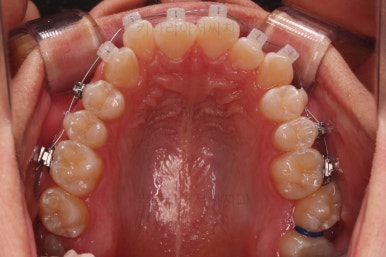

초진 시 입안의 모습입니다.

앞니가 많이 삐뚤고, 송곳니가 부각되어 덧니처럼 보이네요.

장치를 처음 부착한 모습입니다.

순차적으로 장치를 붙여가며 치아를 가지런하게 합니다.

가지런하게 하는 단계를 거친 뒤,당기기 과정에 들어가는데요.

이 과정에서 입이 들어가는 양, 중앙선, 기울기, 앞니 각도 등등 많은 것을 신경써서 당기기를 해주는데요.